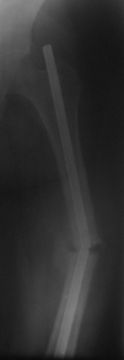

Уважаемые коллеги. Обратилась б-ная Д, 32 г с рефрактурой с/з диафиза левой бедренной кости со сломанным штифтом и с 20-ти дневным новорожденным ребенком на руках.

Со слов 10.11.05 г. оперирована в БСМП , видимо произведена ОИМО штифтом ЦИТО, в то время тоже была беременной, перелом якобы долго не срастался, потом ходила с палочкой, после выкидыша повторно забеременела, поправилась на 14 кг и где-то в середине августа заметила отечность и постепенное искривление бедра, к травматологам не обратилась т.к. её цель была сначала родить ребенка. При осмотре отмечается умеренная отечность, рекурвация и варусное искривление на уровне с/з диафиза бедра, патологической подвижности явно не определяется (ну тугая), умеренная болезненность при пальпации, движения в коленном суставе почти в полном объеме . Дорогие участники форума, коллеги ! Помогите советом!1. Как удалить дистальный обломок штифта? Я знаком с материалом В. Д. Машталова, от 19.10.07г. и рекомендациями А. Н. Челнокова и A. Semenisty, но практически как это делается без рисунков или чертежей не понял, можно ли без ЭОПа делать?.2. На операц. столе одномоментное закрытое устранение деформации, рассверление к/м канала, и ЗИМО более толстым стержнем(не блокируемым)?? Надо учесть, что бедро короткое и толстое, АВФ сложно да и больная не хочет. НВ-62г/л, эритроц- 2,3млн + новорожденный ребенок. Р-снимок пока только один, б-ная отправлена гематологам. С уважением Абдурашид

ХОРОШО НЕ ВИЖУ СЛОМАН ЛИ СТЕРЖЕНЬ ИЛИ НЕТ.

Добрый день. Совсем недавно оперировали очень похожий случай. По-видимому, в Вашем наблюдении сращения и не было. Стержень убрать не будет трудно: его излом проксимальнее линии несращения и при мобилизации конец дистального отломка стержня будет выстоять из кости, ну а проксимальный фрагмент удалите из разреза над грушевидной ямкой без проблем. Мне кажется, нужно сделать реостеосинтез более толстым стержнем с обязательным рассверливанием. Блокировать винтами, динамизировать на столе.

А технически, на мой взгляд, сверхпроблемы нет, штифт, похоже, все-таки сломан, дистальнее рефрактуры костномозговой канал расширяется... Значительные затруднения возможны если штифт целый. Для реостеосинтеза я бы использовал штифт с блокированием, без костной пластики.